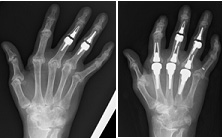

人工指関節

リウマチ指で以前中指・環指PIP関節の人工指関節置換術後、手指の尺側偏位が進行し、痛みと指伸展制限があり手術を希望され、示指から環指までのMP関節の人工指置換術を施行。痛みはなくなり、尺側偏位は軽快し、指の可動域も正常になりました。